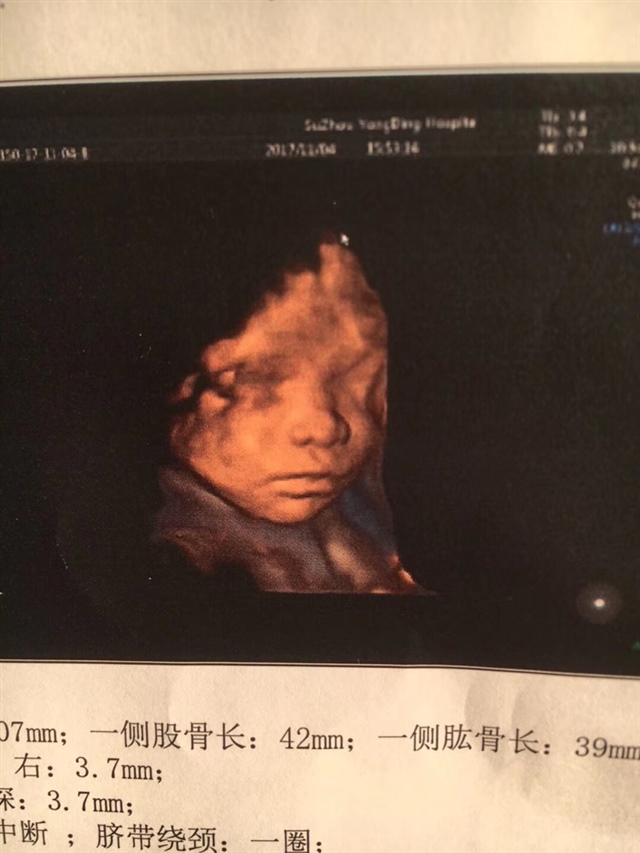

😄我前两星期绕一圈,今天查正常了

A丫丫童装😛[帖主]:我绕两圈估计是没可能绕出来了😅

A丫丫童装😛[帖主]:谢谢🙏我一直左侧卧睡的,绕不出来了马上都足月了太大了!宝宝就是活泼好动型,